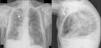

Varón de 75 años, EPOC gradoIV de GOLD, intervenido de lobectomía superior derecha por carcinoma epidermoide pulmonar. Acude al servicio de urgencias por agudización de su EPOC y es ingresado, evolucionando favorablemente las primeras 72h. El cuarto día de ingreso, tras realizar esfuerzo de defecación, presenta disnea y dolor torácico pleurítico izquierdo. En la exploración se aprecia enfisema subcutáneo en la región apical del hemitórax izquierdo. La radiografía de tórax confirmó la presencia de aire a nivel del tejido subcutáneo. Fue tratado con reposo, oxigenoterapia y analgesia, pero el enfisema subcutáneo se extendió por el tórax, la cara, los párpados y el abdomen. Se solicitó una TC torácica, que mostró la presencia de NM y ESC masivo sin evidencia de neumotórax, enfisema pulmonar y ausencia posquirúrgica del lóbulo superior del pulmón izquierdo (fig. 1). Tras 48h el paciente presentó clínica de molestias torácicas, sudoración y presíncope, objetivándose en el electrocardiograma fibrilación auricular paroxística. En esta situación se decide colocar un drenaje subcutáneo derecho (fig. 2). La mejoría clínica fue casi inmediata, pudiendo ser retirado a los 5días. Transcurridos 6meses no se ha producido recidiva.